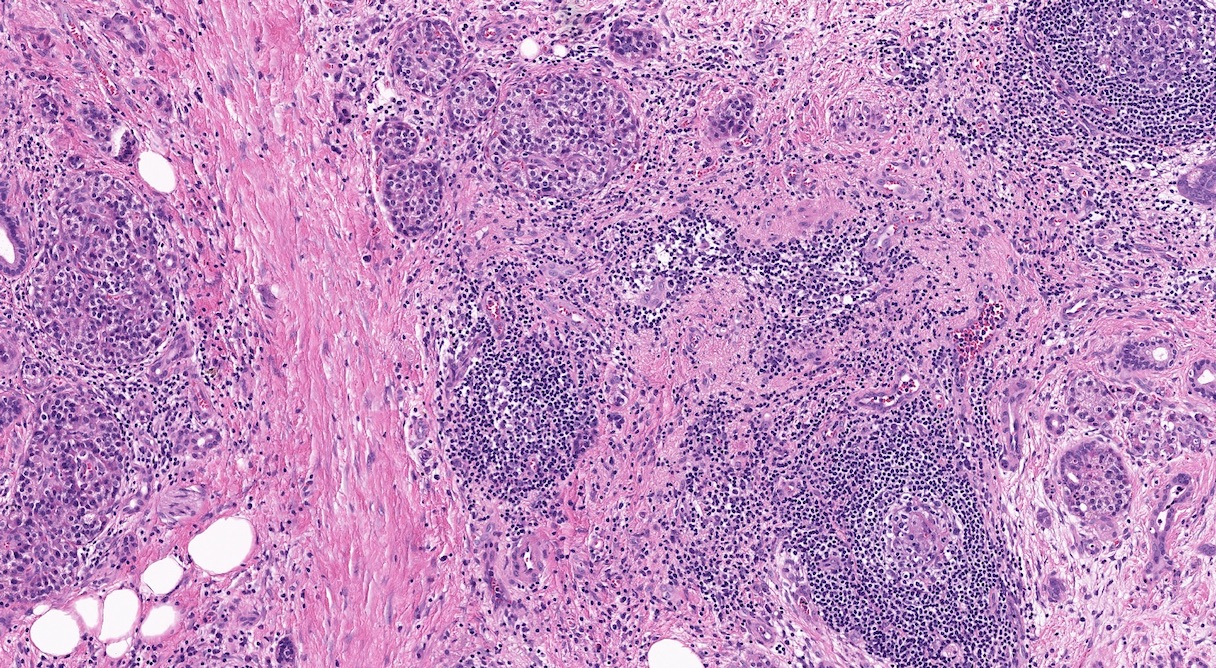

Microscopic (histologic) description

- Triad of cardinal features: fibrosis, loss of acinar tissue, duct changes (Pancreatology 2020;20:586)

- Fibrosis is initially perilobular; during disease progression, it involves the pancreatic lobular units, eventually replacing the acinar parenchyma (so called intralobular fibrosis)

- Ductal changes include distortion of ductal profiles, ectasia, presence of intraluminal concretions of amorphous material (so called protein plugs), squamous metaplasia, intraductal calcification

- Foci of low and high grade pancreatic intraepithelial neoplasia (PanIN) may be encountered

- Foci of periductal chronic inflammation and fat necrosis represent a common finding

Microscopic (histologic) images